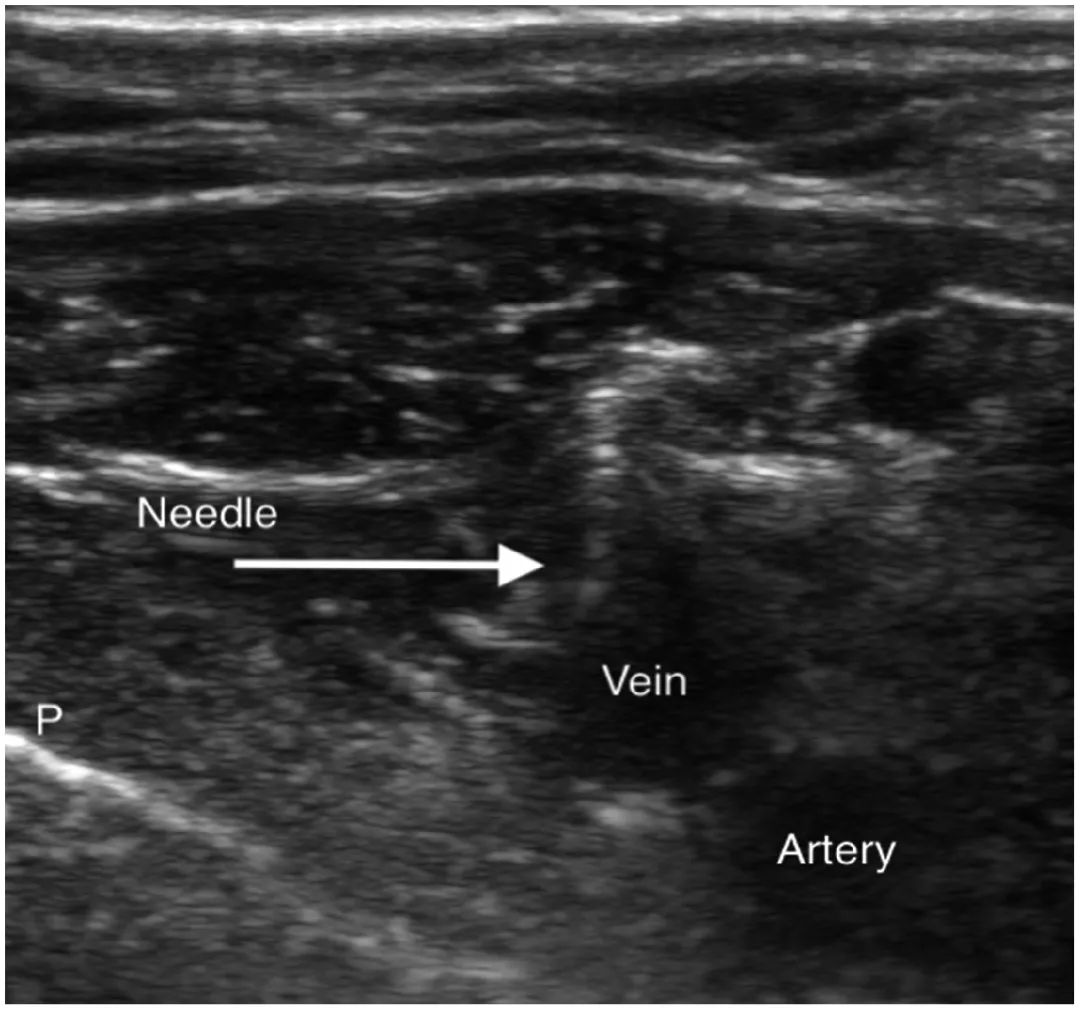

(A)“曲棍球棒”超声探头。(B)用于超声指导腋静脉穿刺的探头和穿刺针的配置。术者位于患者的左侧。左手握住探头,右手握住穿刺针。(C)腋静脉(AV)和腋动脉(AA)的横截面图。肺 (L)也可见。(D)可以看到针尖(实心白色箭头)在腋静脉中前进。(E)在腋静脉腔中看到针尖(白色虚线箭头)。